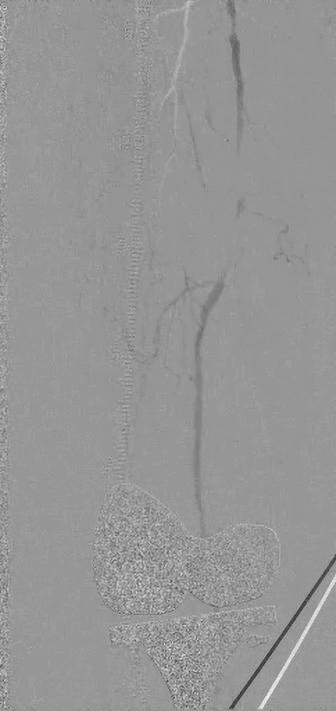

DEEP VEIN

ARTERIALIZATION: MUCH REMAINS TO BE LEARNED BUT USE POISED TO EXPAND IN PATIENTS WITH LESS SEVERE ISCHEMIA

THESE REMAIN EARLY DAYS for transcatheter arterialization of the deep veins (TADV) in the setting of patients with severe chronic limb-threatening ischemia (CLTI), says Daniel Clair, MD, one of the principal investigators in key clinical trials of the procedure, but the learning-curve process promises that “we are going to continue to see slow but not insignificant improvement in results” with the technique.

VEIN ARTERIALIZATION: MUCH REMAINS TO BE LEARNED BUT USE POISED TO EXPAND IN PATIENTS WITH LESS SEVERE ISCHEMIA

All patients enrolled in the trial had Rutherford class 5/6 disease, with a total of 105 CLTI patients undergoing the procedure between 2018 and 2022. At VIVA, Clair reported a limb salvage rate of 65% and improvement in Rutherford classification: 65.8% of patients had class 4 or below and 54.3% had class 0. Wounds were completely healed/healing in 82% of patients and the mean pain score was 1.2 out of 10. When combined with the PROMISE I trial, the two-year limb salvage rate was 68%, with no differences observed based on age, sex, race, baseline Rutherford classification, diabetes or dialysis, Clair had added.

Those type of data are likely to be built upon, with the future portending wider use of TADV, Clair reflects in a recent interview with Vascular Specialist

“What is likely is that you are going to see an expansion in the use of this technology in patients who perhaps are not as far down the path of ischemia as we have seen,” he explains. “I also think that there will likely be some complementary role in terms of arterial revascularization in people who have very bad distal disease.”

The data show that 25–30% continue to lose their limbs even when TADV is used, so opportunities to enhance benefits from the procedure require exploration, Clair continues. “The use of deep vein arterialization with

vascular growth factors to enhance angiogenesis in the foot might be ideal. Right now, we are trying to understand how to optimize the venous flow in the foot to enhance, expedite and speed up the arterialization and delivery of oxygen to the tissues in the foot so we don’t lose the forefoot or toes, but we get them this delivery of oxygenated blood so they can heal the wounds that they have. Part of what we’re doing is trying to look at the angiographic and duplex data from PROMISE I and II patients to see if we can identify who are the patients who did really well and the patients who did not do well, and can we identify differences between them.”

Clair is clear on this direction of travel. The patient population who informed the clinical trials typify the necessity of the procedure, he says. “In the past, essentially everyone I have enrolled in these trials is a patient who likely would have had an amputation, and I can say that because I have watched them worsen before enrolling them, having tried other measures to help get them through. In the PROMISE trials, we carried this out in what I call the sickest of this group of patients, because they had to be externally validated as having no option; they had to be more than a month out from any previous angiogram or attempted intervention; and they had to have a wound on their foot in order to allow them to qualify. One of the critical issues now is, while that was what the trial was, in the community this technology is being used more in patients who don’t have good options, but who get an angiogram, can’t have percutaneous intervention, and the next day they are going for this venous arterialization.”

believers in the technology start to embrace it and make referrals. His previous involvement in angiogenesis trials underscore how sick the PROMISE patients are, he says: in those, patients who had rest pain, severe claudication, and no foot wound could be enrolled. “[PROMISE trial participants] are patients who have not been studied in any previous trial because, frankly, they are sicker than any company was willing to look at, particularly in interventional trials.”

Some form of forefoot amputation is not unusual in the first two to three months after TADV, nor is an increase in pain in the first month, PROMISE data reveal.

“It’s unusual for these patients to keep everything because they have such severe disease in the foot by the time they present for treatment with this therapy,” Clair points out.

“Intriguingly, in PROMISE I, with every patient who kept their limb, if they made it three months with their limb on, they were going to keep their limb for the long term. In PROMISE II, there were very few patients who lost their limb beyond that first three-to-four-month period. If you get a good venous arterialization, and you see a response through six to 10 weeks, these people are likely going to keep their limb.”

Meanwhile, PROMISE III will take another extended look at the same group of patients “in a little more real-world applications,” Clair adds. “So many of these patients have bilateral limb ischemia, so we included patients in whom you could do the procedure on both sides. We did not mandate an independent review committee; we did not mandate a 30-day waiting period between a previous angiogram or attempted intervention and moving on to venous arterialization.”